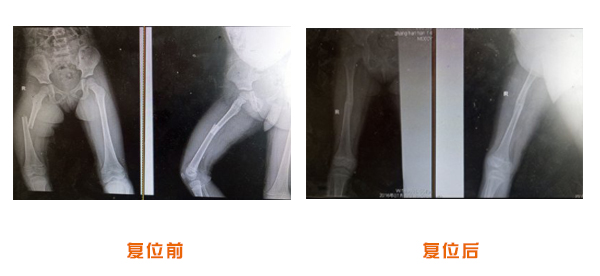

踝關節脫位骨折治療前后對比